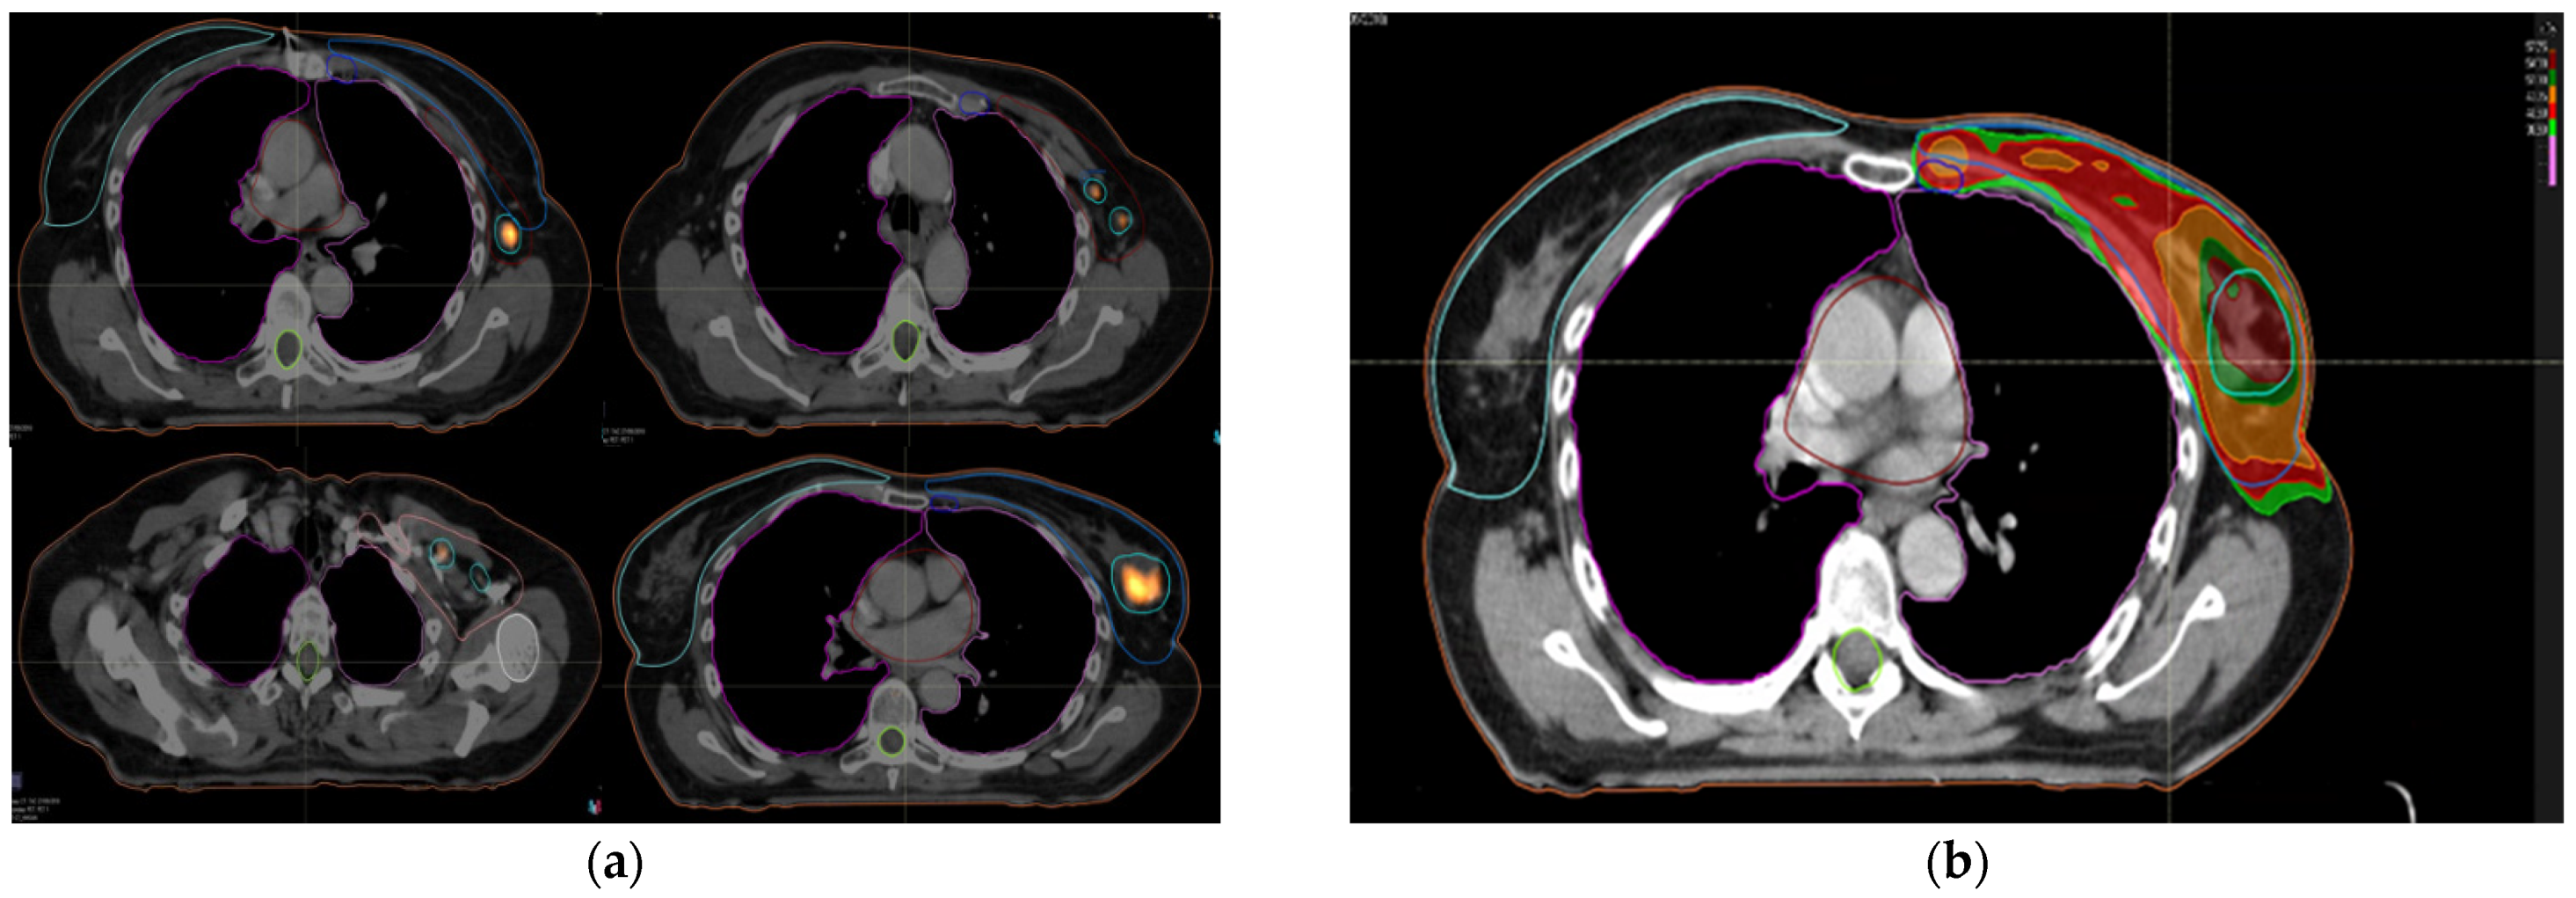

Whole breast, lymph node levels I–IV and ipsilateral internal mammary chain when indicated were identified in addition to enhanced macroscopic tumor on simulation 18FDG-PET-CT. The ipsilateral and contralateral lungs, heart and the contralateral breast volume were outlined as organs at risk. The prescribed radiation dose was 40.5 Gy in 15 fractions of 2.7 Gy, five fractions per week, to whole breast and locoregional lymph node levels with simultaneous integrated boost up to 54 Gy in 15 fractions of 3.6 Gy to macroscopic tumor areas highlighted by 18FDG-PET (Figure 1a,b).

Figure 1.

(a) contours on planning 18FDG-PET-CT; (b) dosimetric planning with VMAT.